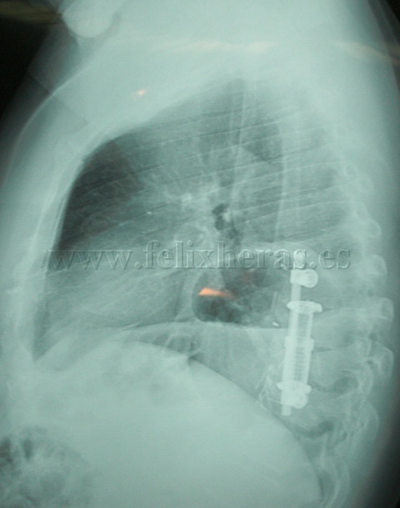

Hernia diafragmática traumática